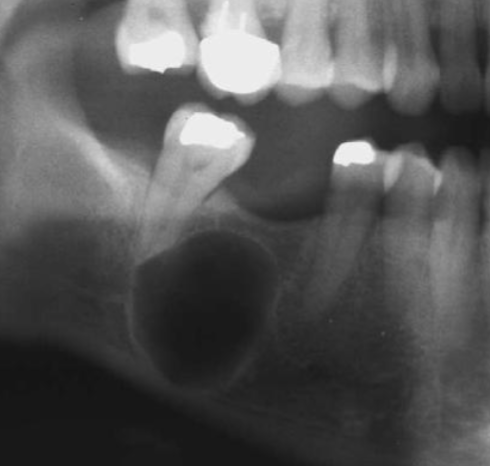

scalloping

radiolucent lesion that extends between the roots, seen in traumatic bone cyst (TBC)